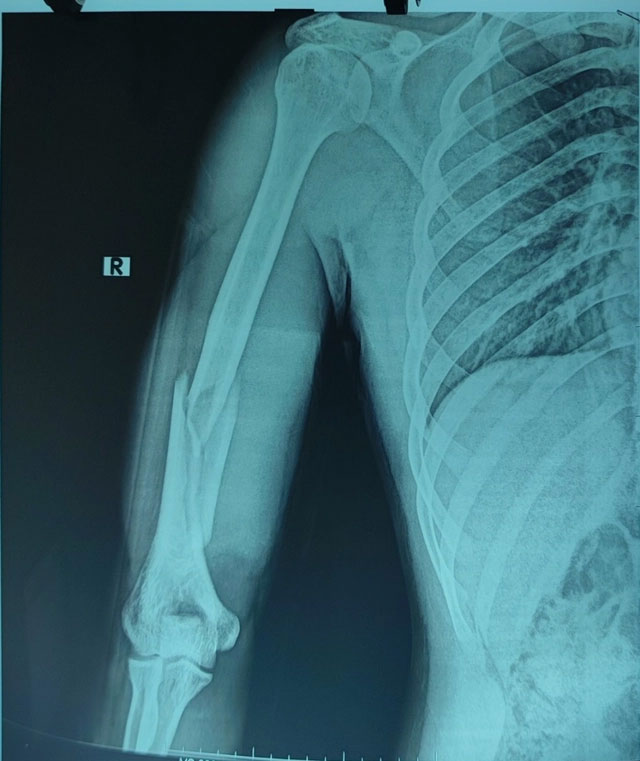

Anh C nhập viện trong tình trạng sưng đau, biến dạng, hạn chế vận động cánh tay phải. Vận động bàn ngón tay bình thường, không yếu liệt, hình ảnh X-quang cho thấy xương cánh tay phải gãy chéo vát ở 1/3 dưới có mảnh rời cánh bướm lớn.

Các bác sĩ chẩn đoán nam thanh niên bị gãy kín xương cánh tay phải không liệt quay, chỉ định phẫu thuật kết hợp xương nẹp vít.

Sau phẫu thuật kết hợp xương nẹp vít, người bệnh được chụp X-quang kiểm tra sau mổ, giải phẫu xương cánh tay được phục hồi, người bệnh ra viện sau 4 ngày.